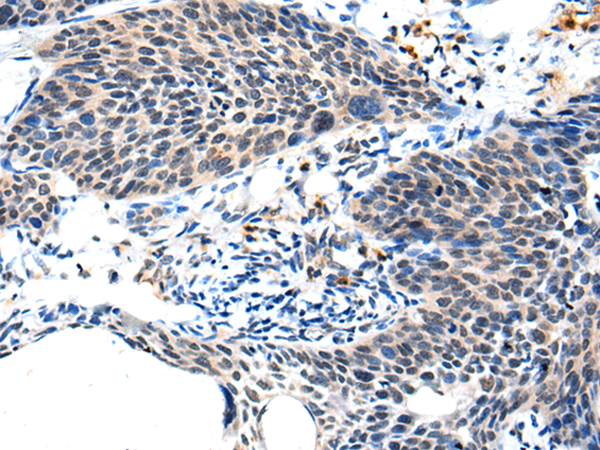

ELISA, IHC |

IHC positive control: |

Human cervical cancer and human tonsil |

IHC Recommend dilution: |

25-100 |